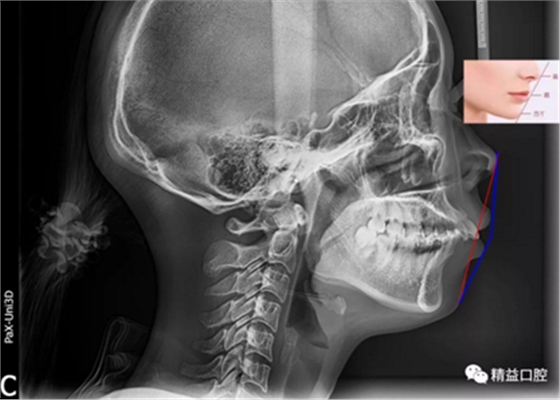

矯正前后面部對比圖,不僅改善了嘴凸的問題,最最重要的是

下巴!下巴!下巴!一條完美的曲線正從我們眼前劃過~~~